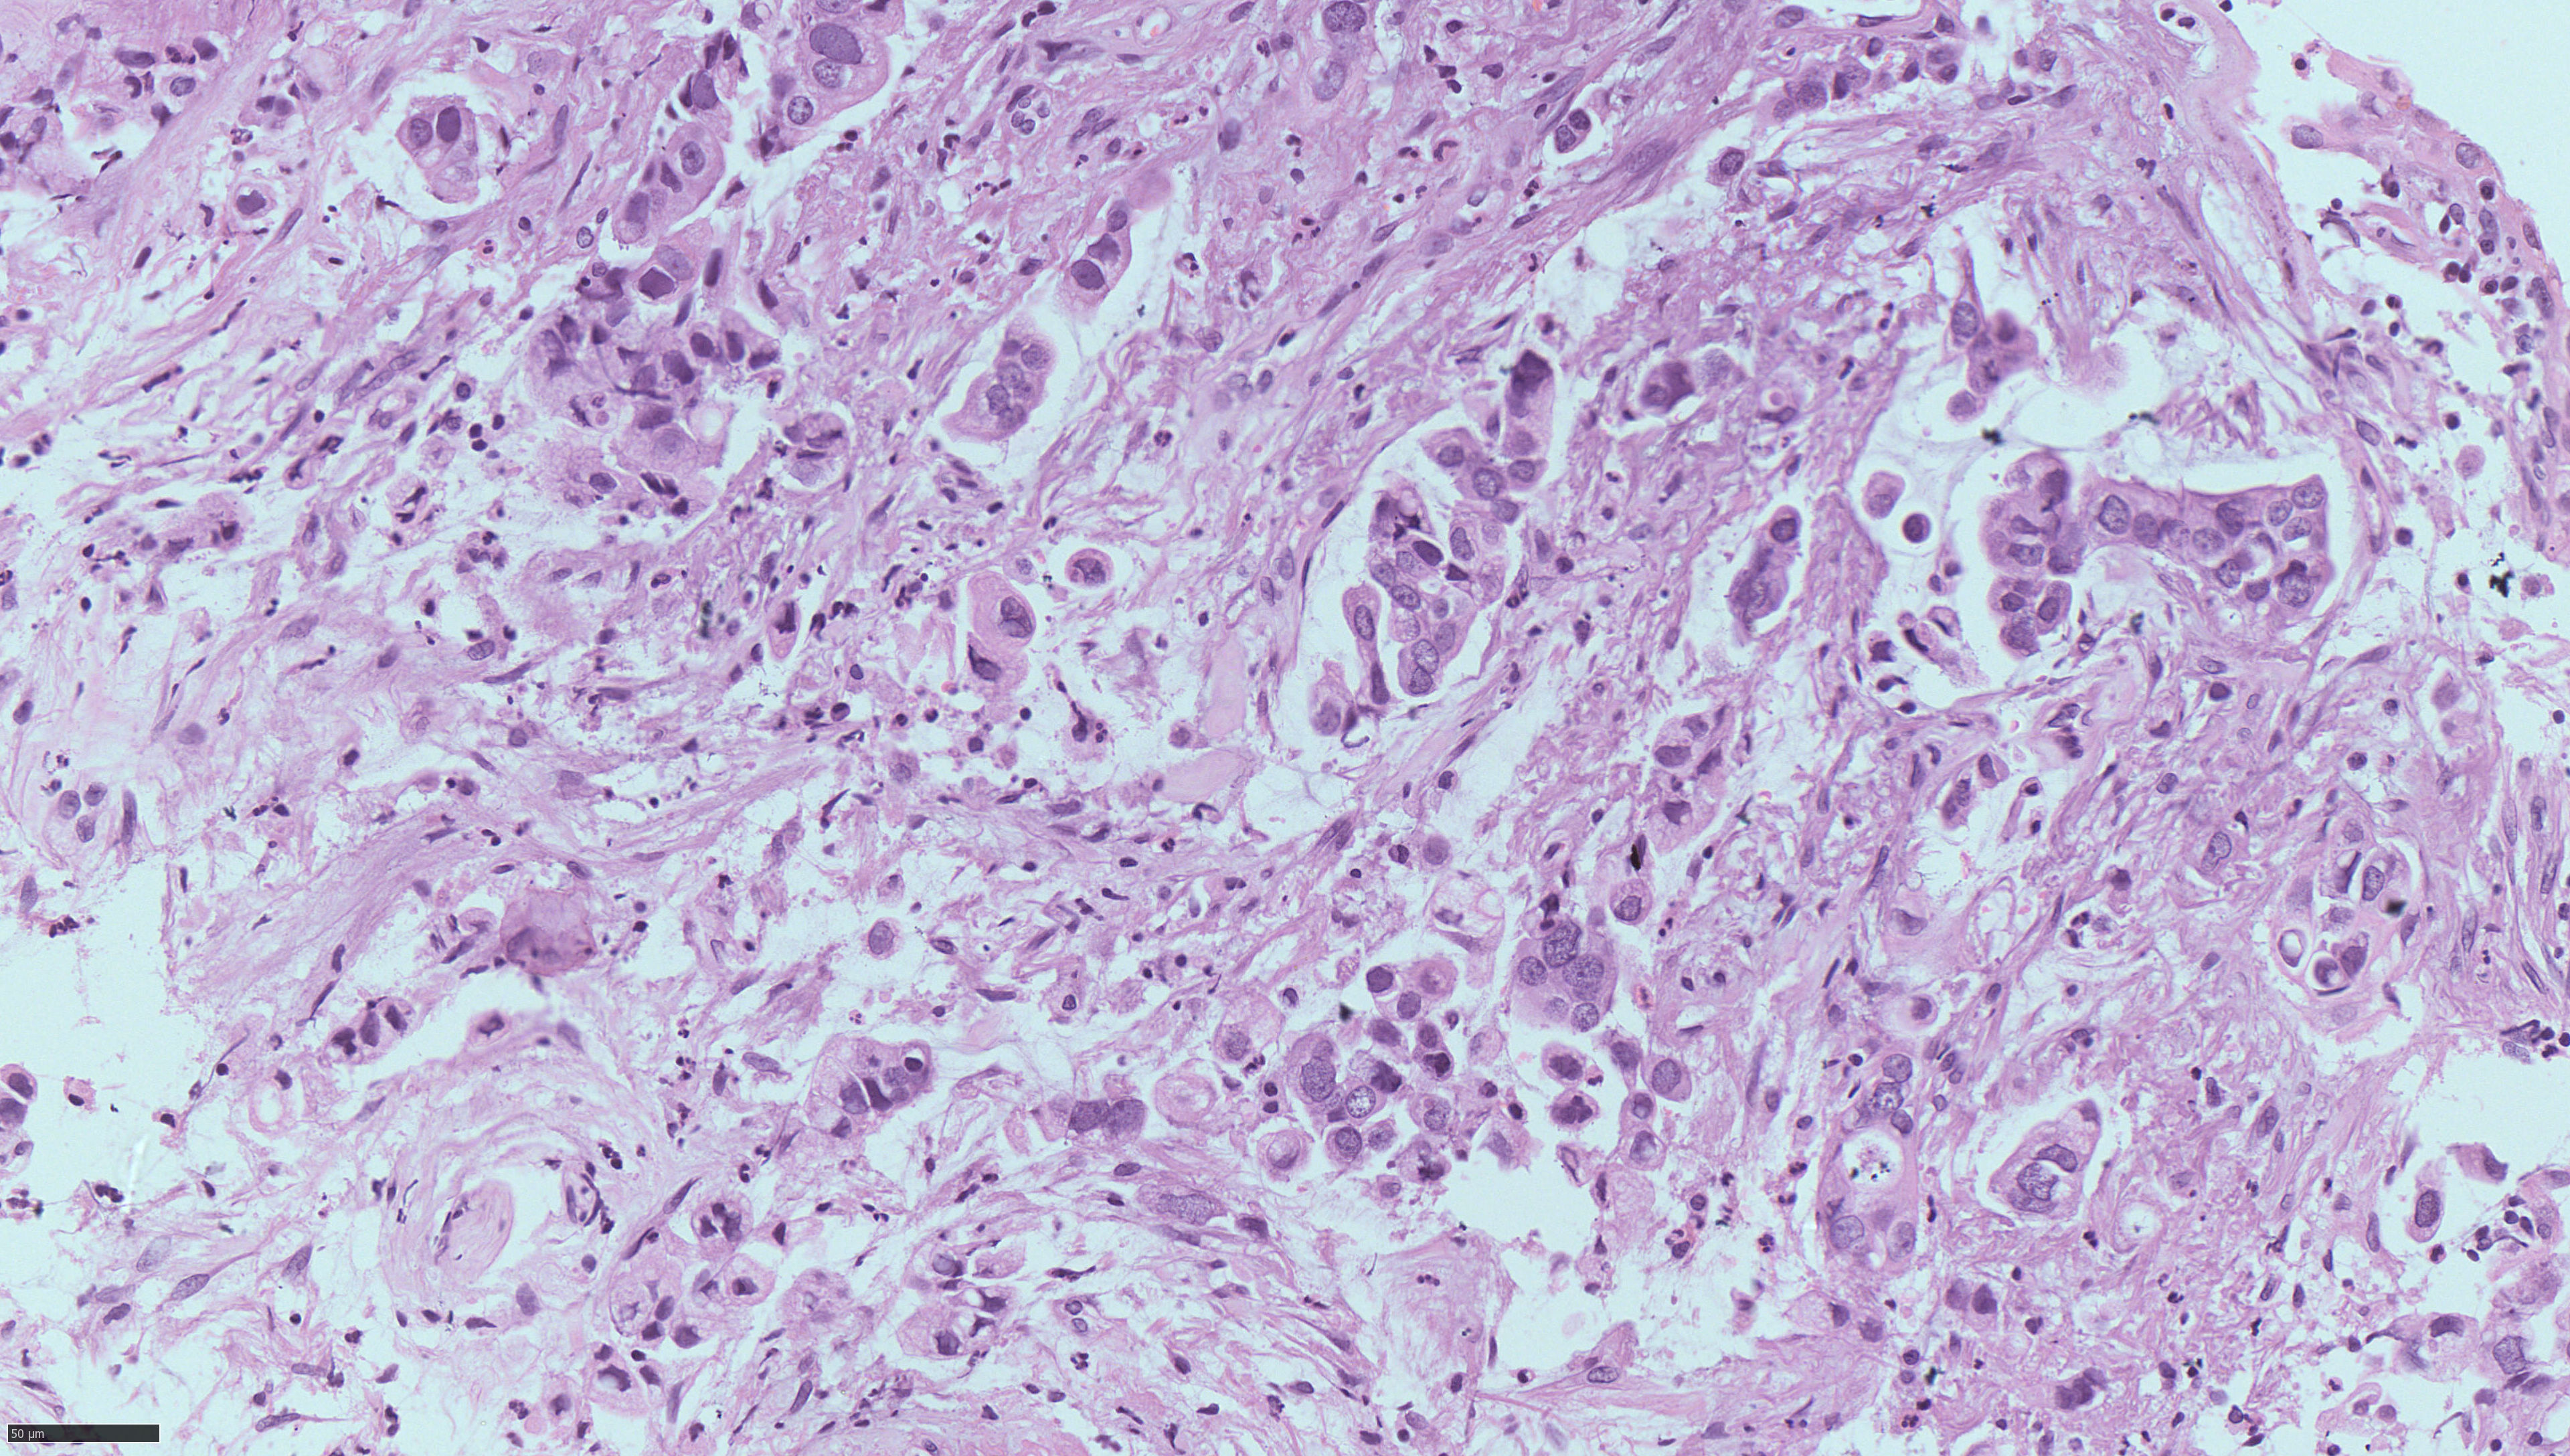

Image Gallery & Slides

Pathology images, lab photos and recent slides. Replace these with higher resolution images from your collection when ready.

To add more images: put your files into the images/ folder and update the <img src="images/yourfile.jpg"> paths below.